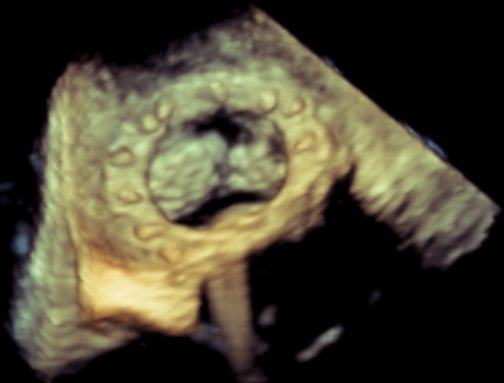

术中影像监护与评估(DSA&TEE)

CDFI提示过瓣血流通畅

CDFI示少量瓣周漏

收缩期未见瓣周漏

左房内未见对比剂显影